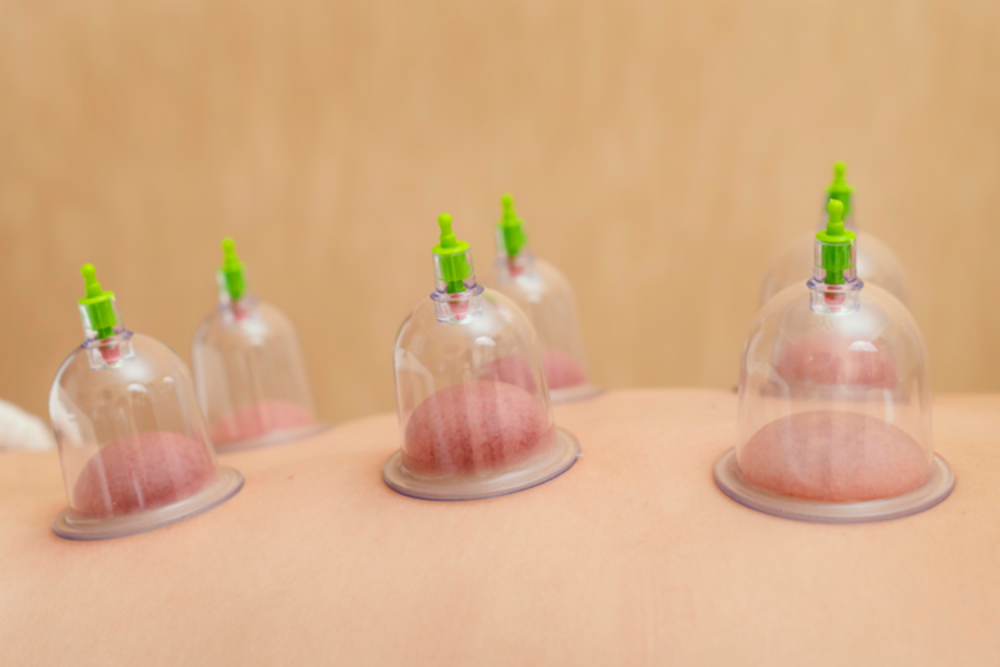

Cupping therapy is an ancient healing method that uses special cups to create suction on the skin. Many people seek cupping therapy for pain relief,

Cupping therapy is an ancient healing practice. It uses special cups placed on the skin to create suction. Many people try cupping therapy for pain

Cupping therapy is a popular treatment used in physiotherapy clinics today. Many people seek cupping therapy for pain relief and faster healing. In fact, this

What Is Cupping Therapy? Cupping therapy is an ancient healing practice. It uses special cups placed on the skin to create suction. This method has

In our fast-paced world, people are increasingly turning to alternative therapies for stress relief, pain management, and overall well-being. One such practice gaining popularity is

An ancient form of alternative medicine involves placing cups on the skin to create a vacuum, drawing the skin and underlying tissue into the cup.